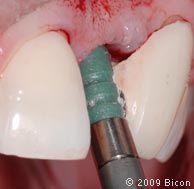

55. Производится полировка интегрированной коронки с помощью акрилового диска.

56. Вид интегрированной коронки в устройстве для установки коронок. Изготовление пластмассового посадочного шаблона.

57. Установка IAC с новыми контурами.